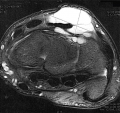

Les progrès techniques de la chirurgie mini-invasive du poignet ont permis de réaliser l'ablation de ces kystes sous arthroscopie, c'est-à-dire au moyen de deux mini incisions permettant, l'une d'introduire une caméra de 1,9 à 2,7 mm de diamètre et l'autre des instruments mécaniques et de radiofréquence de 2-3 mm de diamètre (figure 2). La base d'implantation du kyste est repérée (une IRM ou une échographie préalable ont guidé le choix des petits incisions-figure 3) et retirée. Le liquide mucoïde s'écoule alors dans l'articulation et est aspiré alors que la paroi du kyste est excisée par la profondeur sans nécessité d'incision supplémentaire (figure 4). On visualise ainsi les tendons extenseurs des doigts et du poignet qui doivent être contrôlés et protégés durant toute l'intervention (figure 5), constituant le seul risque spécifique de cette arthroscopie. l'intérêt de cette technique n'est pas qu'esthétique, bien que l'indication du geste opératoire soit essentiellement cosmétique (figure 6) mais surtout plus logique et efficace que la chirurgie dite classique, car il permet le repérage et l'excision du point de départ de cette "tumeur" bénigne, diminuant ainsi le risque théorique de récidive. On peut ainsi diagnostiquer et retirer des petits kystes du ligament scapho-lunaire (figure 7), il y a encore peu surnommés "occult ganglions" car peu accessibles aux autres procédés d'exploration du poignet, ils peuvent être douloureux notamment lors des appuis en flexion dorsale.